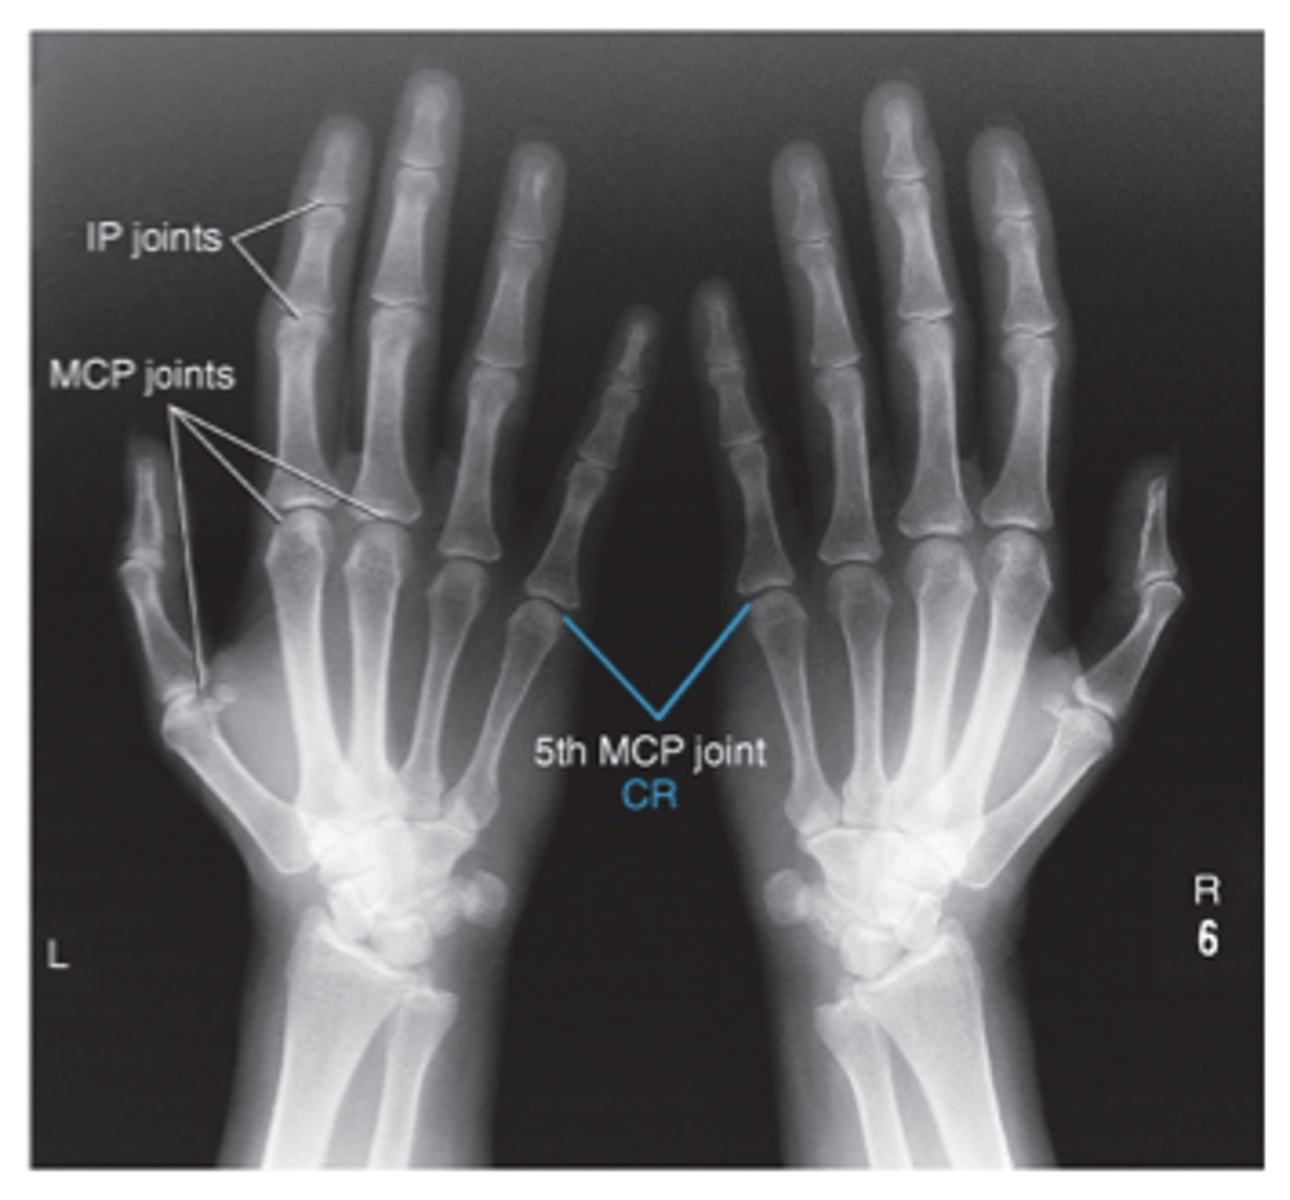

Ap oplique Bilateral hands